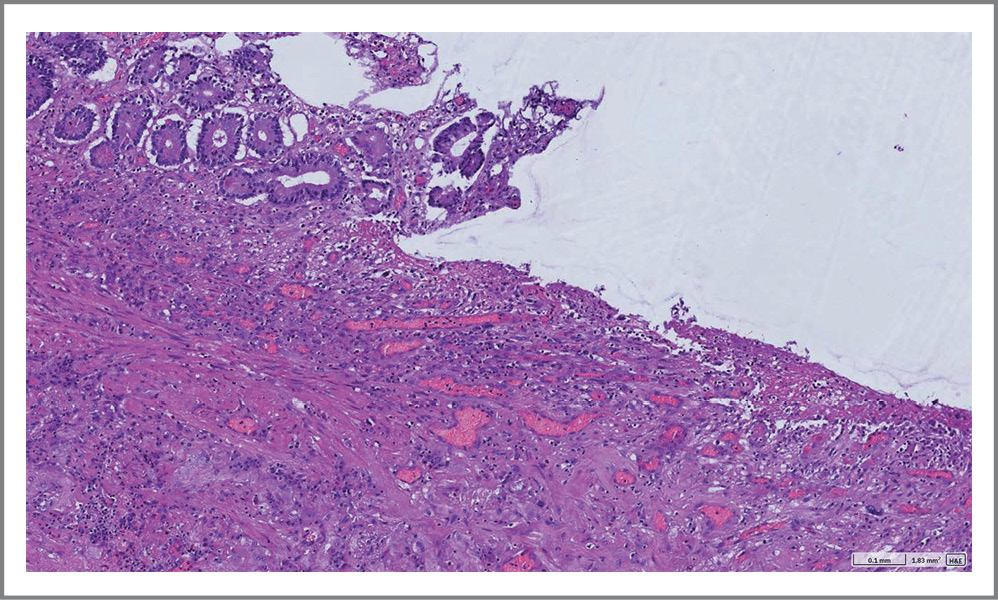

Проведено микроскопическое исследование операционного препарата. Обнаружены фрагменты стенки ТК с язвенным дефектом глубиной до подслизистой основы, занимающим около 50% окружности СО. Дно дефекта представлено фиброзно-склеротической тканью со зрелой грануляционной тканью, наложениями фибрина и гранулоцитов по поверхности. СО в краях дефекта с очагами псевдопилорической метаплазии. Артерии и артериолы в дне дефекта с очагами гиалиноза. Мышечный слой стенки и серозная оболочка типичного морфологического строения. В жировой клетчатке брыжейки обнаружен лимфоузел с реактивными изменениями.

Заключение. Микроскопическая картина характерна для хронической язвы ТК с активным воспалением, началом формирования фиброзной стриктуры (рис. 5–8).

Рис. 5. Микроскопические изменения в стенке резецированной ТК. Псевдопилорическая метаплазия в краях язвенных дефектов ТК на фоне хронического воспаления.

Fig. 5. Microscopic changes in the wall of the resected jejunum. Pseudopyloric metaplasia in the edges of ulcerative defects of the jejunum with chronic inflammation.

Рис. 7. Микроскопические изменения в стенке резецированной ТК. Псевдопилорическая метаплазия в краях язвенных дефектов ТК на фоне хронического воспаления.

Fig. 7. Microscopic changes in the wall of the resected jejunum. Pseudopyloric metaplasia in the edges of ulcerative defects of the jejunum with chronic inflammation.